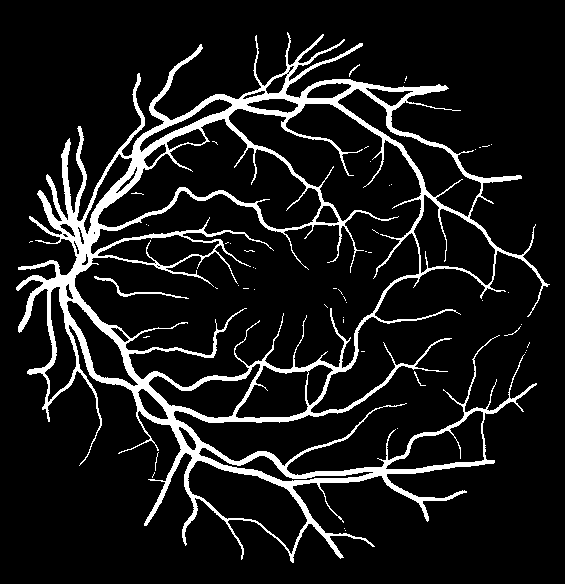

Using the final pretrained student SegRAVIR model in our knowledge distillation framework described in Section IV-D, we fine-tuned and tested the network on three publicly available datasets of color images, DRIVE [10], STARE [9], and CHASE_DB1 [12]. Fig. 7 shows example of SegRAVIR segmentation outputs on DRIVE and CHASE_DB1 datasets. Table VII presents a quantitative comparison between the segmentation performance of our SegRAVIR model and state-of-the-art models: R2U-Net [25], DU-Net [26], and IterNet [34]. By all evaluation metrics, SegRAVIR has achieved new state-of-the-art results on the DRIVE, STARE [9], and CHASE_DB1 datasets.